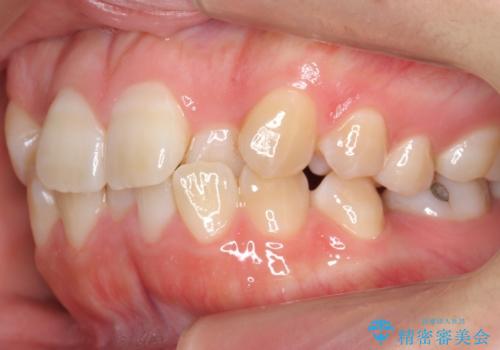

よくある悩み 前歯が裏に2本入っているのを治したい

- 前歯が2本裏に入ってしまっているのを治したいとのことでした。